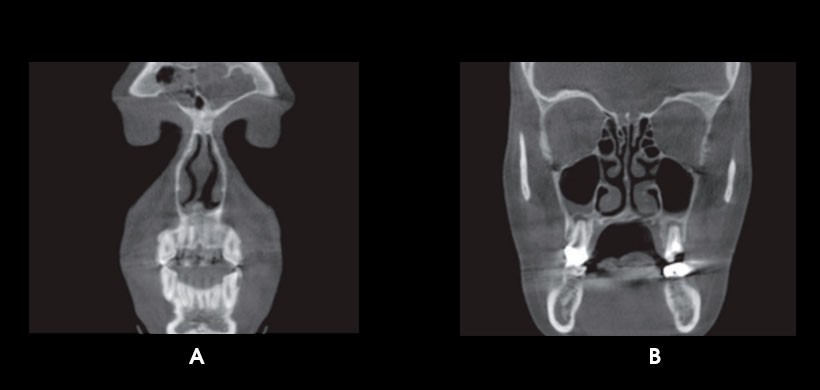

Fig 2. CBCT. A) quiste de retención mucoso en seno maxilar derecho. B) Osteoma en seno etmoidal izquierdo.